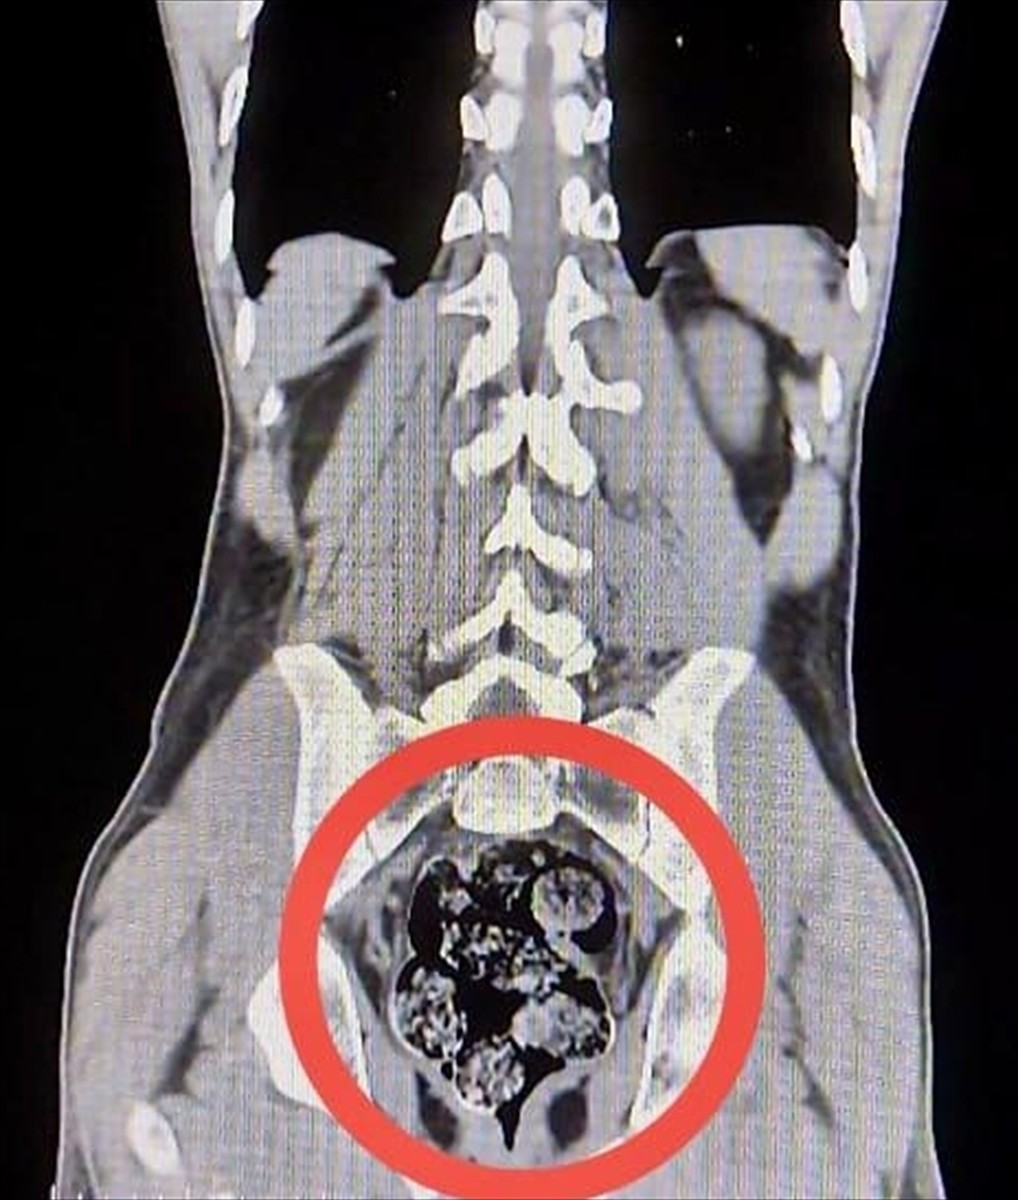

Yapılan üst aramalarında, zanlıların üzerinde uyuşturucu madde bulunamadı. Ancak, Harakani Devlet Hastanesine sevk edilen Amır Rafıeı S'nin mide ve bağırsaklarında yapılan tetkikler sonucunda 7 parça halinde 203,02 gram sentetik uyuşturucu maddesi tespit edildi.